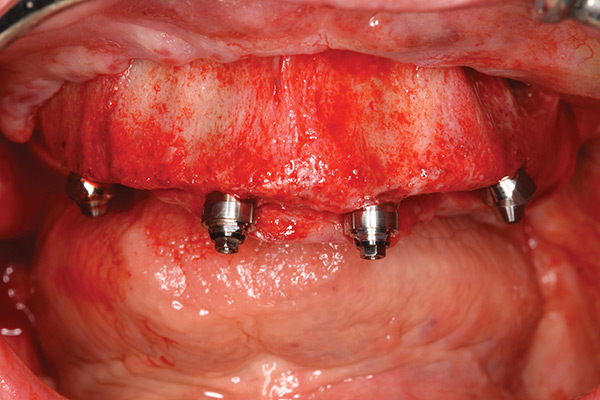

The transmucosal abutments are then placed onto the implants using either straight or 17-degree multi-unit abutments and 30-degree angulated abutments with different collar heights (Figure 4). Abutments should be orientated so that the screw access is in a favorable position. Bone grafts can be used to augment any exposed threads, extractions, sockets, or other localized defects. The tissues should be carefully repositioned and sutured to form a tight seal around the abutments.

Fig 4. Placement of implants with straight multi-unit abutments on anterior implants and 30-degree angulated abutments posteriorly.

Figure 4